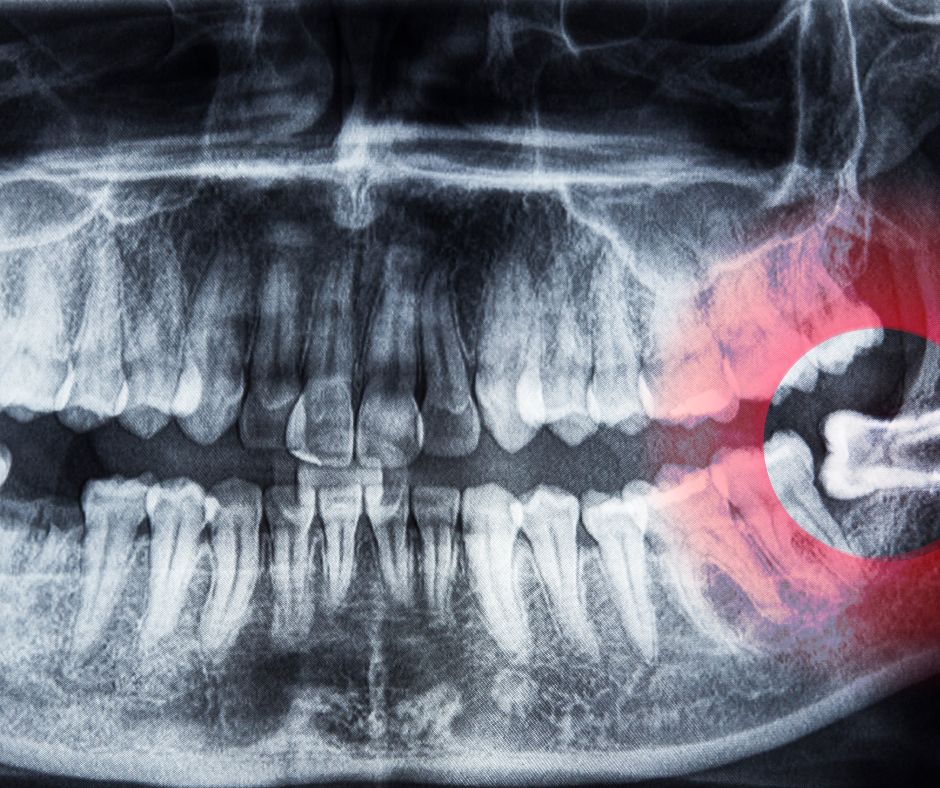

- Impacted (partially or fully trapped) wisdom teeth

- Clinical Examination & Digital Imaging To assess tooth position, root structure, and proximity to nerves.